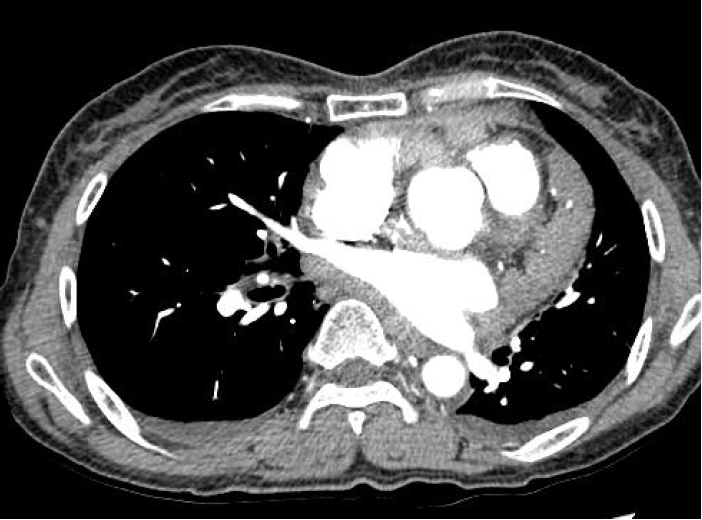

Figure 2.

Chest CT image shows multiple nodular mass with diffuse thickening of pericardium. Normal lung parenchyma is noted.

59세의 여자 환자가 2개월간 지속된 호흡곤란, 두근거림과 부종을 증상으로 본원 순환기내과에 내원하였다. 내원 당시 환자의 과거력상 특이소견이 없었고, 이학적 검사에서 양측 하지에 경도의 부종이 있었다. 내원 후 시행한 흉부 방사선 검사에서 경도의 심비대가 관찰되었다(그림 1). 심초음파 검사에서는 우심방과 우심실의 비대가 있었다. 흉부 전산화단층 촬영 검사에서 심막이 미만성으로 두꺼워져 있으며 불균일한 다발성 종괴가 심막을 따라서 관찰되었고, 폐 실질에는 이상소견이 보이지 않았다(그림 2). 심막에서 발생한 종괴를 의심하였고, 정확한 진단을 위해서는 조직 검사가 필요하였다. 환자는 전신마취하에 우측 개흉술을 시행하였고, 수술 소견상 심막이 미만성으로 두꺼워져 있고, 다발성 결절들이 촉지되었고, 심장과 심막과의 유착이 있었다. 우심방을 싸고 있는 심막의 결절에서 조직을 얻었고, 크기는 2×2 cm였다. 조직학적 검사 결과 상피세포 형태의 악성 중피종으로 진단되었다(그림 3). 조직검사 결과 후 시행한 양전자 전산화 단층촬영에서 심막에 미만성으로 높은 대사의 섭취(standard uptake value=6.18)가 관찰되었고, 개흉술에 의한 흉골에 국소적 대사 섭취 외에 다른 부위의 높은 대사의 섭취는 보이지 않았다(그림 4). 영상학적 검사와 조직학적 검사를 종합한 최종 진단은 심막에서 기원한 원발성 악성 중피종이다.